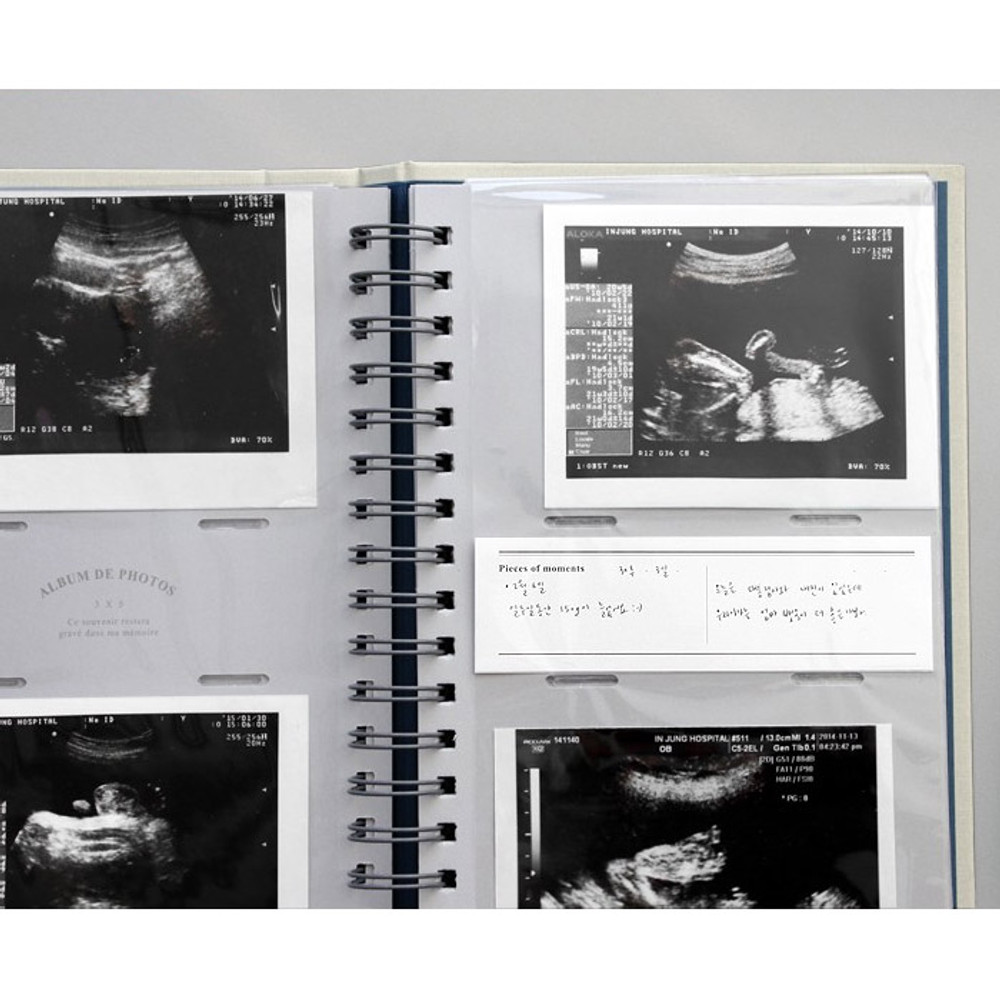

Iconic Album de photos 3X5 slip in photo album by ICONIC. The Album de photos photo album is a well made and useful slip in album. This photo album allows you to store up to 100 photos by inserting them into these frames. A purchase also includes white label papers. Keep your precious stories forever with this album.